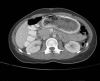

Figure 2.

Axial computed tomography demonstrating gastric bezoar in lumen of stomach with extension to duodenum.